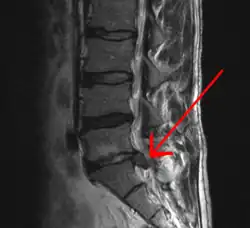

Imaging is indicated when there are red flags, ongoing neurological symptoms that do not resolve, or ongoing or worsening pain.[5] In particular, early use of imaging (either MRI or CT) is recommended for suspected cancer, infection, or cauda equina syndrome.[5] MRI is slightly better than CT for identifying disc disease; the two technologies are equally useful for diagnosing spinal stenosis.[5] Only a few physical diagnostic tests are helpful.[5] The straight leg raise test is almost always positive in those with disc herniation,[5] and lumbar provocative discography may be useful to identify a specific disc causing pain in those with chronic high levels of low back pain.[47] Therapeutic procedures such as nerve blocks can also be used to determine a specific source of pain.[5] Some evidence supports the use of facet joint injections, transforminal epidural injections and sacroiliac injections as diagnostic tests.[5] Most other physical tests, such as evaluating for scoliosis, muscle weakness or wasting, and impaired reflexes, are of little use.[5]

Complaints of low back pain are one of the most common reasons people visit doctors.[48][49] For pain that has lasted only a few weeks, the pain is likely to subside on its own.[50] Thus, if a person's medical history and physical examination do not suggest a specific disease as the cause, medical societies advise against imaging tests such as X-rays, CT scans, and MRIs.[49] Individuals may want such tests but, unless red flags are present,[51][52] they are unnecessary health care.[48][50] Routine imaging increases costs, is associated with higher rates of surgery with no overall benefit,[53][54] and the radiation used may be harmful to one's health.[53] Fewer than 1% of imaging tests identify the cause of the problem.[48] Imaging may also detect harmless abnormalities, encouraging people to request further unnecessary testing or to worry.[48] Even so, MRI scans of the lumbar region increased by more than 300% among United States Medicare beneficiaries from 1994 to 2006.[10]